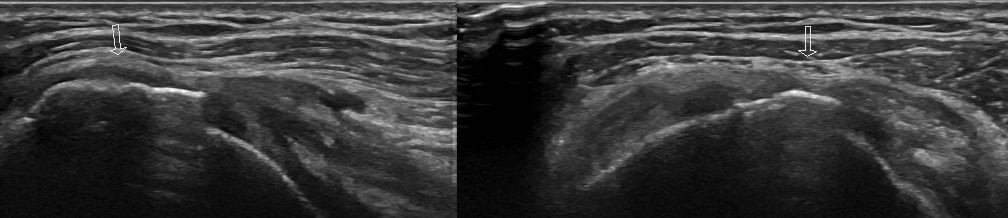

回旋筋腱板の解説をAIに頼む

ChatGPTが一般にリリースされたときには、解剖学的な内容を聞いてもデタラメな情報しか得られなかった。そのころのChatGPTの回答はこんな感...